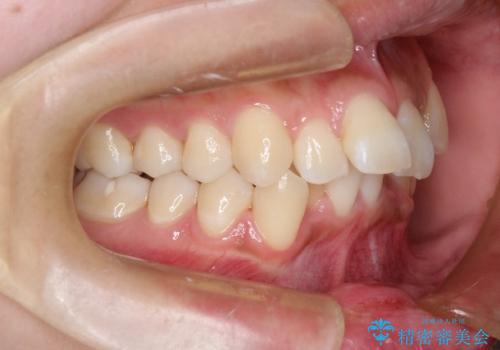

非抜歯で整える前歯の矯正

- 患者様は、前歯の重なり(叢生)が気になるとのことでご来院されました。診断の結果、奥歯を後方に移動することで前歯にスペースを確保し、非抜歯で歯列を整える方針としました。治療には審美性の高いホワイトワイヤーを使用し、奥歯の遠心移動にはリンガルアーチを装着しました。治療期間は約2年を予定し、月に一度の調整を通じて歯の動きを細かく管理しました。

非抜歯矯正は、歯を抜かずに自然な歯列を作るため、歯列全体のバランスを考慮する必要があります。本症例では、リンガルアーチによる奥歯の遠心移動を用いましたが、初期段階で軽い違和感を覚える方もいらっしゃいます。そのため、装置装着後のケアや食生活について詳しく説明を行い、患者様にも協力いただきました。また、審美ワイヤーを使用することで、日常生活での見た目のストレスを軽減し、治療を快適に進めることができました。